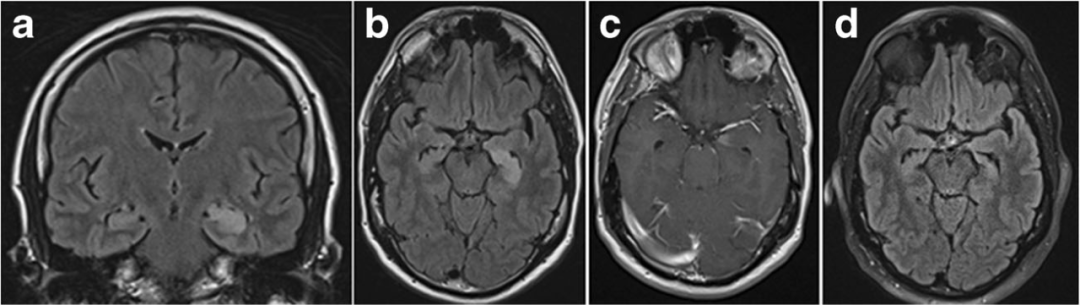

7、单纯疱疹病毒脑炎:预后差,致死率高,常累及单侧或者双侧内侧颞叶,包括海马,不及时治疗进展加重。MR:单侧或颞叶内侧(包括海马)长 T1 长 T2 信号,扩散可受限或不受限

1周后

8、边缘性脑炎:常见于副肿瘤综合征(小细胞肺癌、乳腺癌),癫痫及行为异常。MR:单侧或颞叶内侧(包括海马)长 T1 长 T2 信号,扩散可受限或不受限